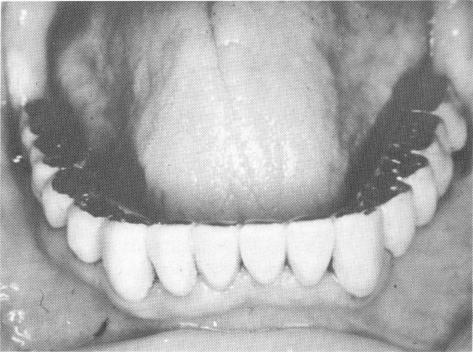

The remaining mandibular teeth were prepared for full crown restorations, and blade implants were placed in both posterior edentulous areas (Fig. 15-105) . A full arch fixed prosthesis was fabricated and cemented over the implants and teeth (Fig. 15-106) .

Fig. 15-106. The full arch fixed prosthesis cemented in position.